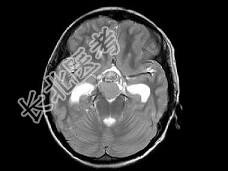

- 单项选择题男,15岁, 2个月前无明显诱因出现头痛,间断性钝痛, 根据所提供图像,最可能的诊断是 ( )

A、垂体瘤

B、颅咽管瘤(造釉细胞型)

C、生殖细胞瘤

D、胶质细胞瘤

E、结核性肉芽肿